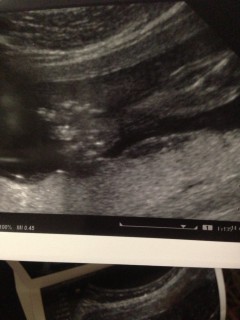

手のひらと腕の写真です。来週で7ヶ月目です、先月は時々しか感じなかった胎動も今では毎日感じられるようになったので、頑張って生きてるんだなと安心します。赤ちゃんが出来た事は嬉しいですが、何よりも旦那さんとの間に子供が出来た事が本当に本当に嬉しく思います。